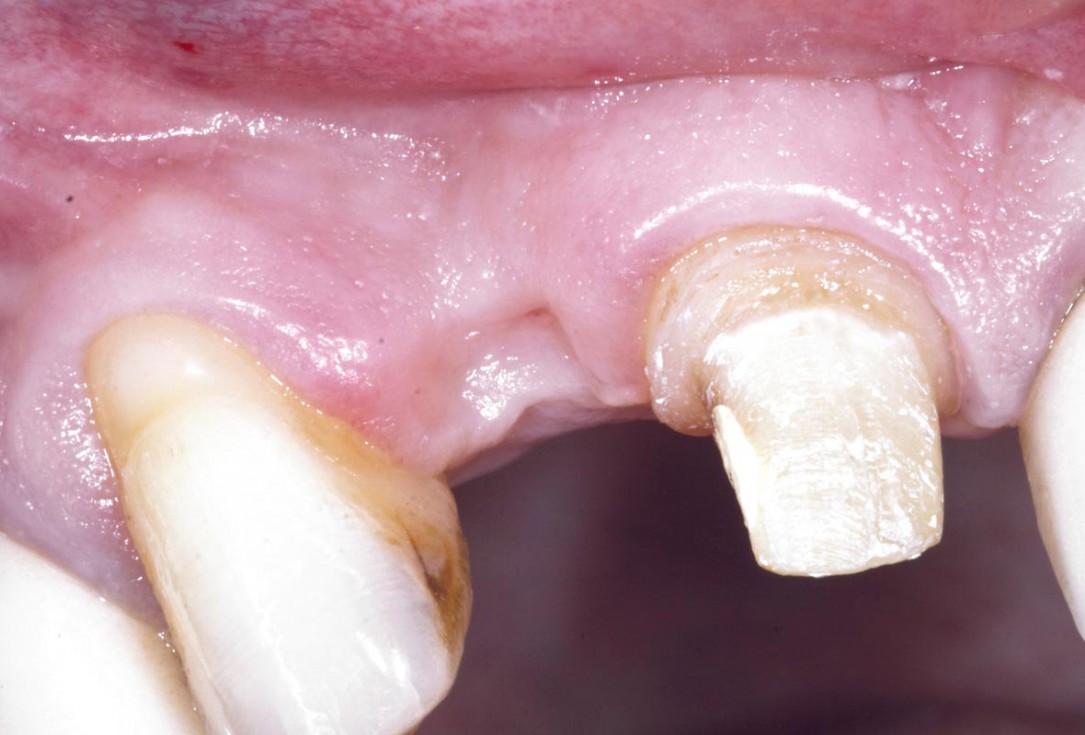

6/19 - Site without prosthetics showing sever buccal bone lossBone augementation with maxresorb® - Dr. R. Cutts